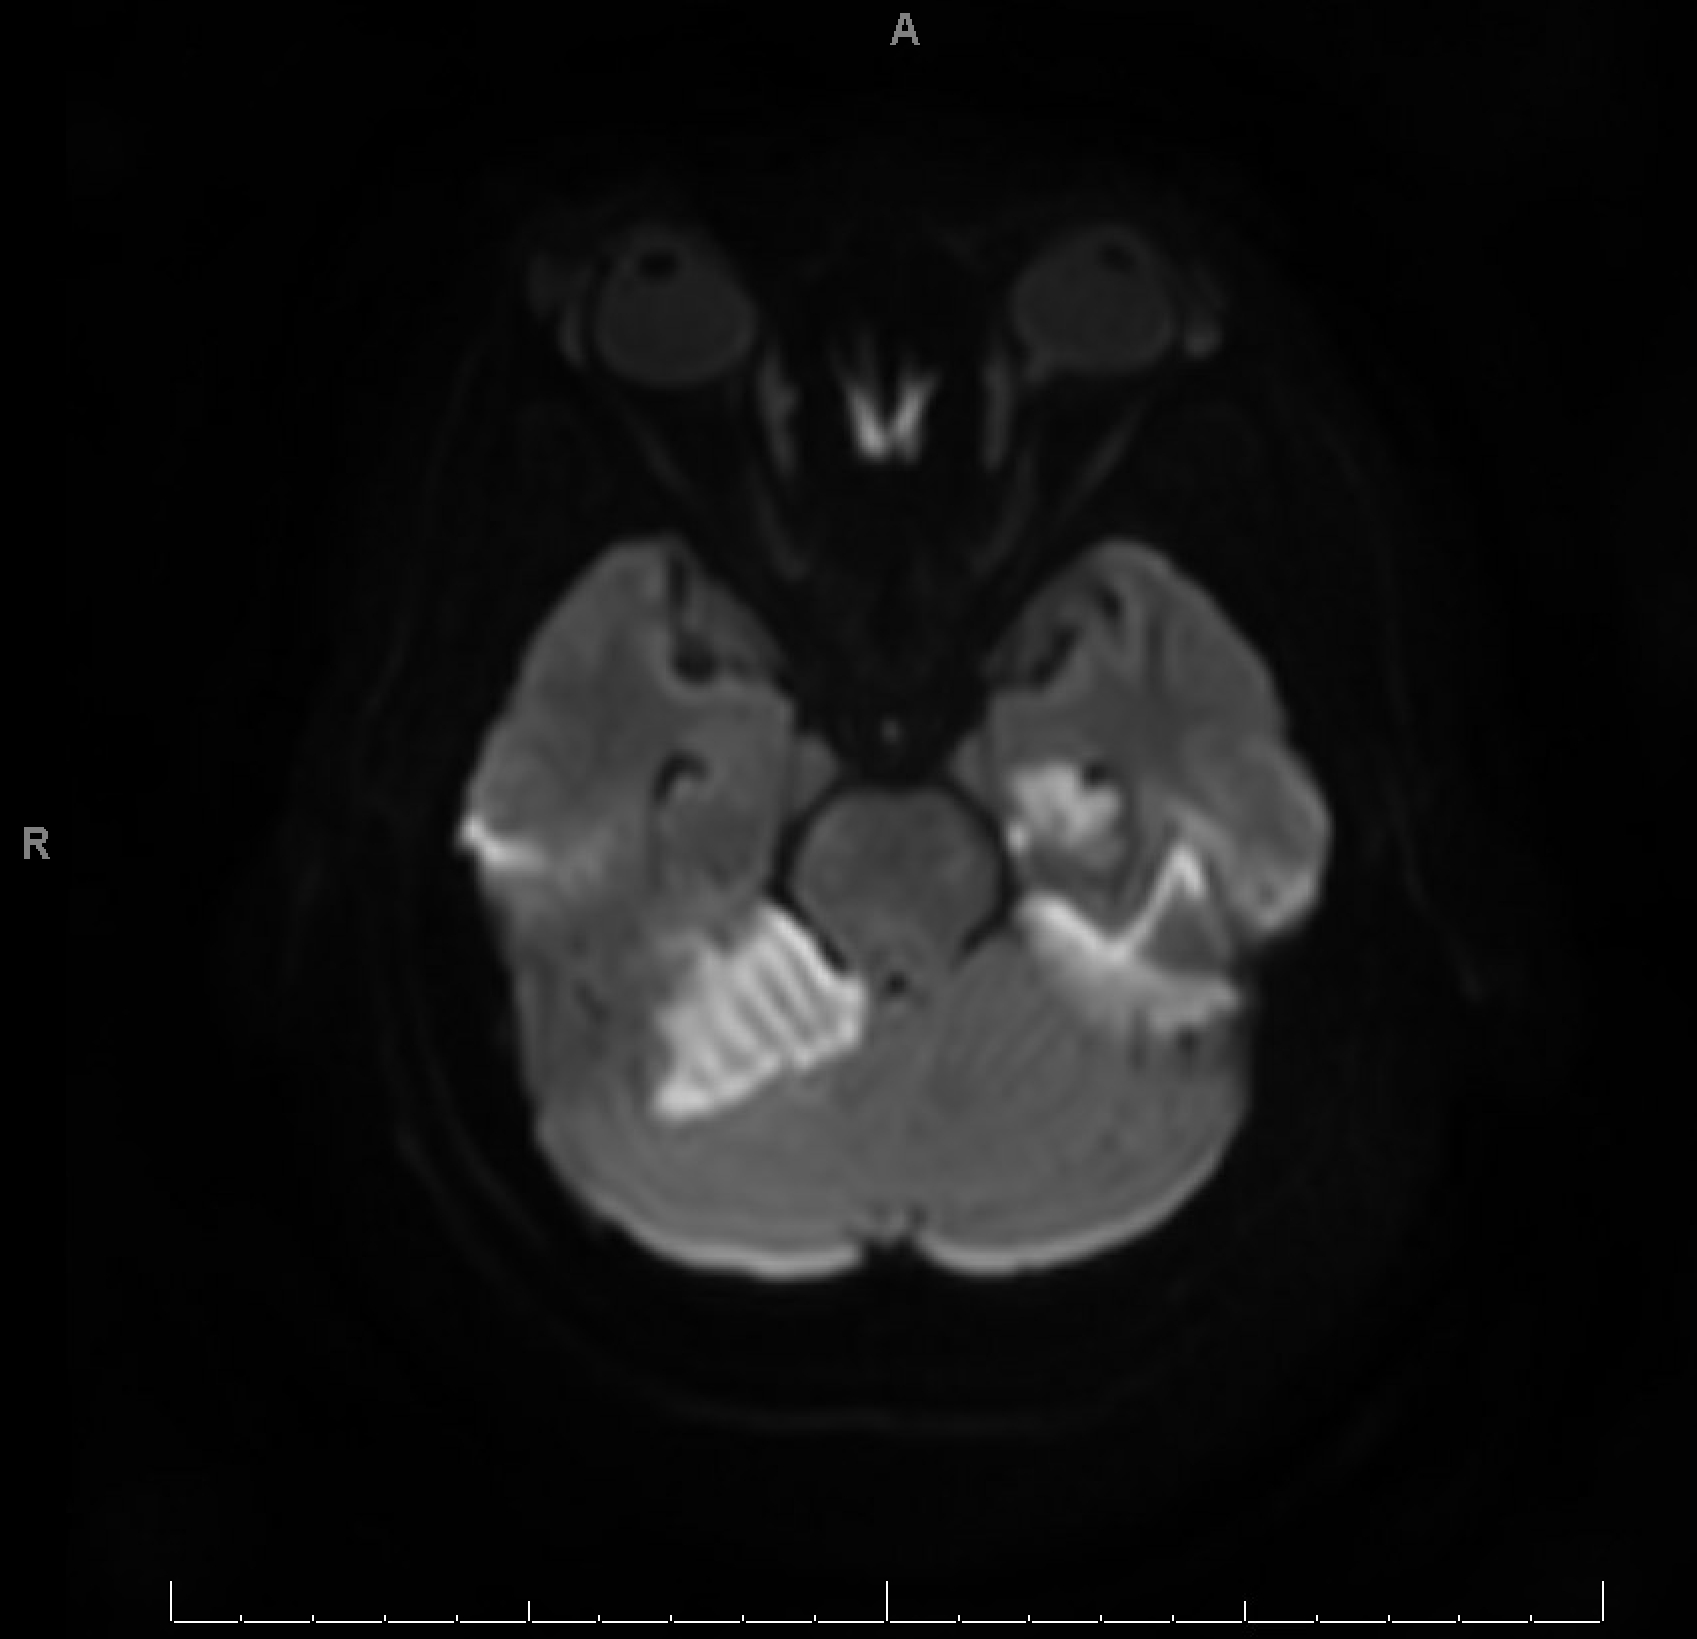

CTA revealed bilateral PCA stenosis, likely due to vasospasm. MRI brain showed bilateral occipital, left mesial temporal, and right cerebellar vasogenic edema with areas of restricted diffusion and microhemorrhages, supporting the diagnosis of PRES. Workup for infection, vasculitis, and autoimmune encephalitis was negative. Hypertensive emergency was suspected as the precipitating factor.

This case underscores the diagnostic complexity of PRES, which can mimic stroke, infection, or structural lesions. Imaging, particularly MRI, is pivotal in distinguishing PRES from infarction. The presence of seizures, encephalopathy, and visual disturbances in the setting of malignant hypertension should prompt immediate consideration of PRES, especially when imaging suggests posterior white matter involvement. This case highlights the urgency of BP control and the need for a multidisciplinary approach, including neurology, radiology, and critical care, to prevent long-term neurological sequelae.